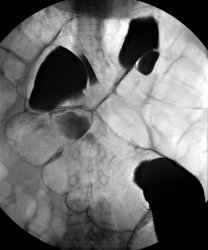

Данная пациентка(60 лет) была направлена к концу недели на исключение органической патологии, могу сказать исследование затянулось до получаса. Газ не вводился, снимки делались без предворительного увеличения.

Пациентка мне показалась интересна в плане демонстрационного случая долихомегаколона сигмовидного отдела ободочной кишки, на самом деле ей проводили и до меня ирригоскопию и ФКС по месту жительства, эндоскопическая картина совпадает с данной рентгенологической, эндоскописты описали "сигму" сравнивая её с мешком. Видно гипотонию и сглаженность гаустрации сигмовидного отдела ободочной кишки, поперечник значительно увеличен, можно отметить удлинение и дополнительный изгиб.

А газ на самом деле не вводился, да и подготовка желает лучшего, восходящий отдел я так и четко не увидел, а мои 400мл рентген-контрастного вещества как капля в море, пришлось ещё 1 литр вводить.

Да кстати, в данном случае можно считать метода была традиционной, 1,5 литра рентген-контрастного вещества, а правые отделы забиты кишечным содержимым.